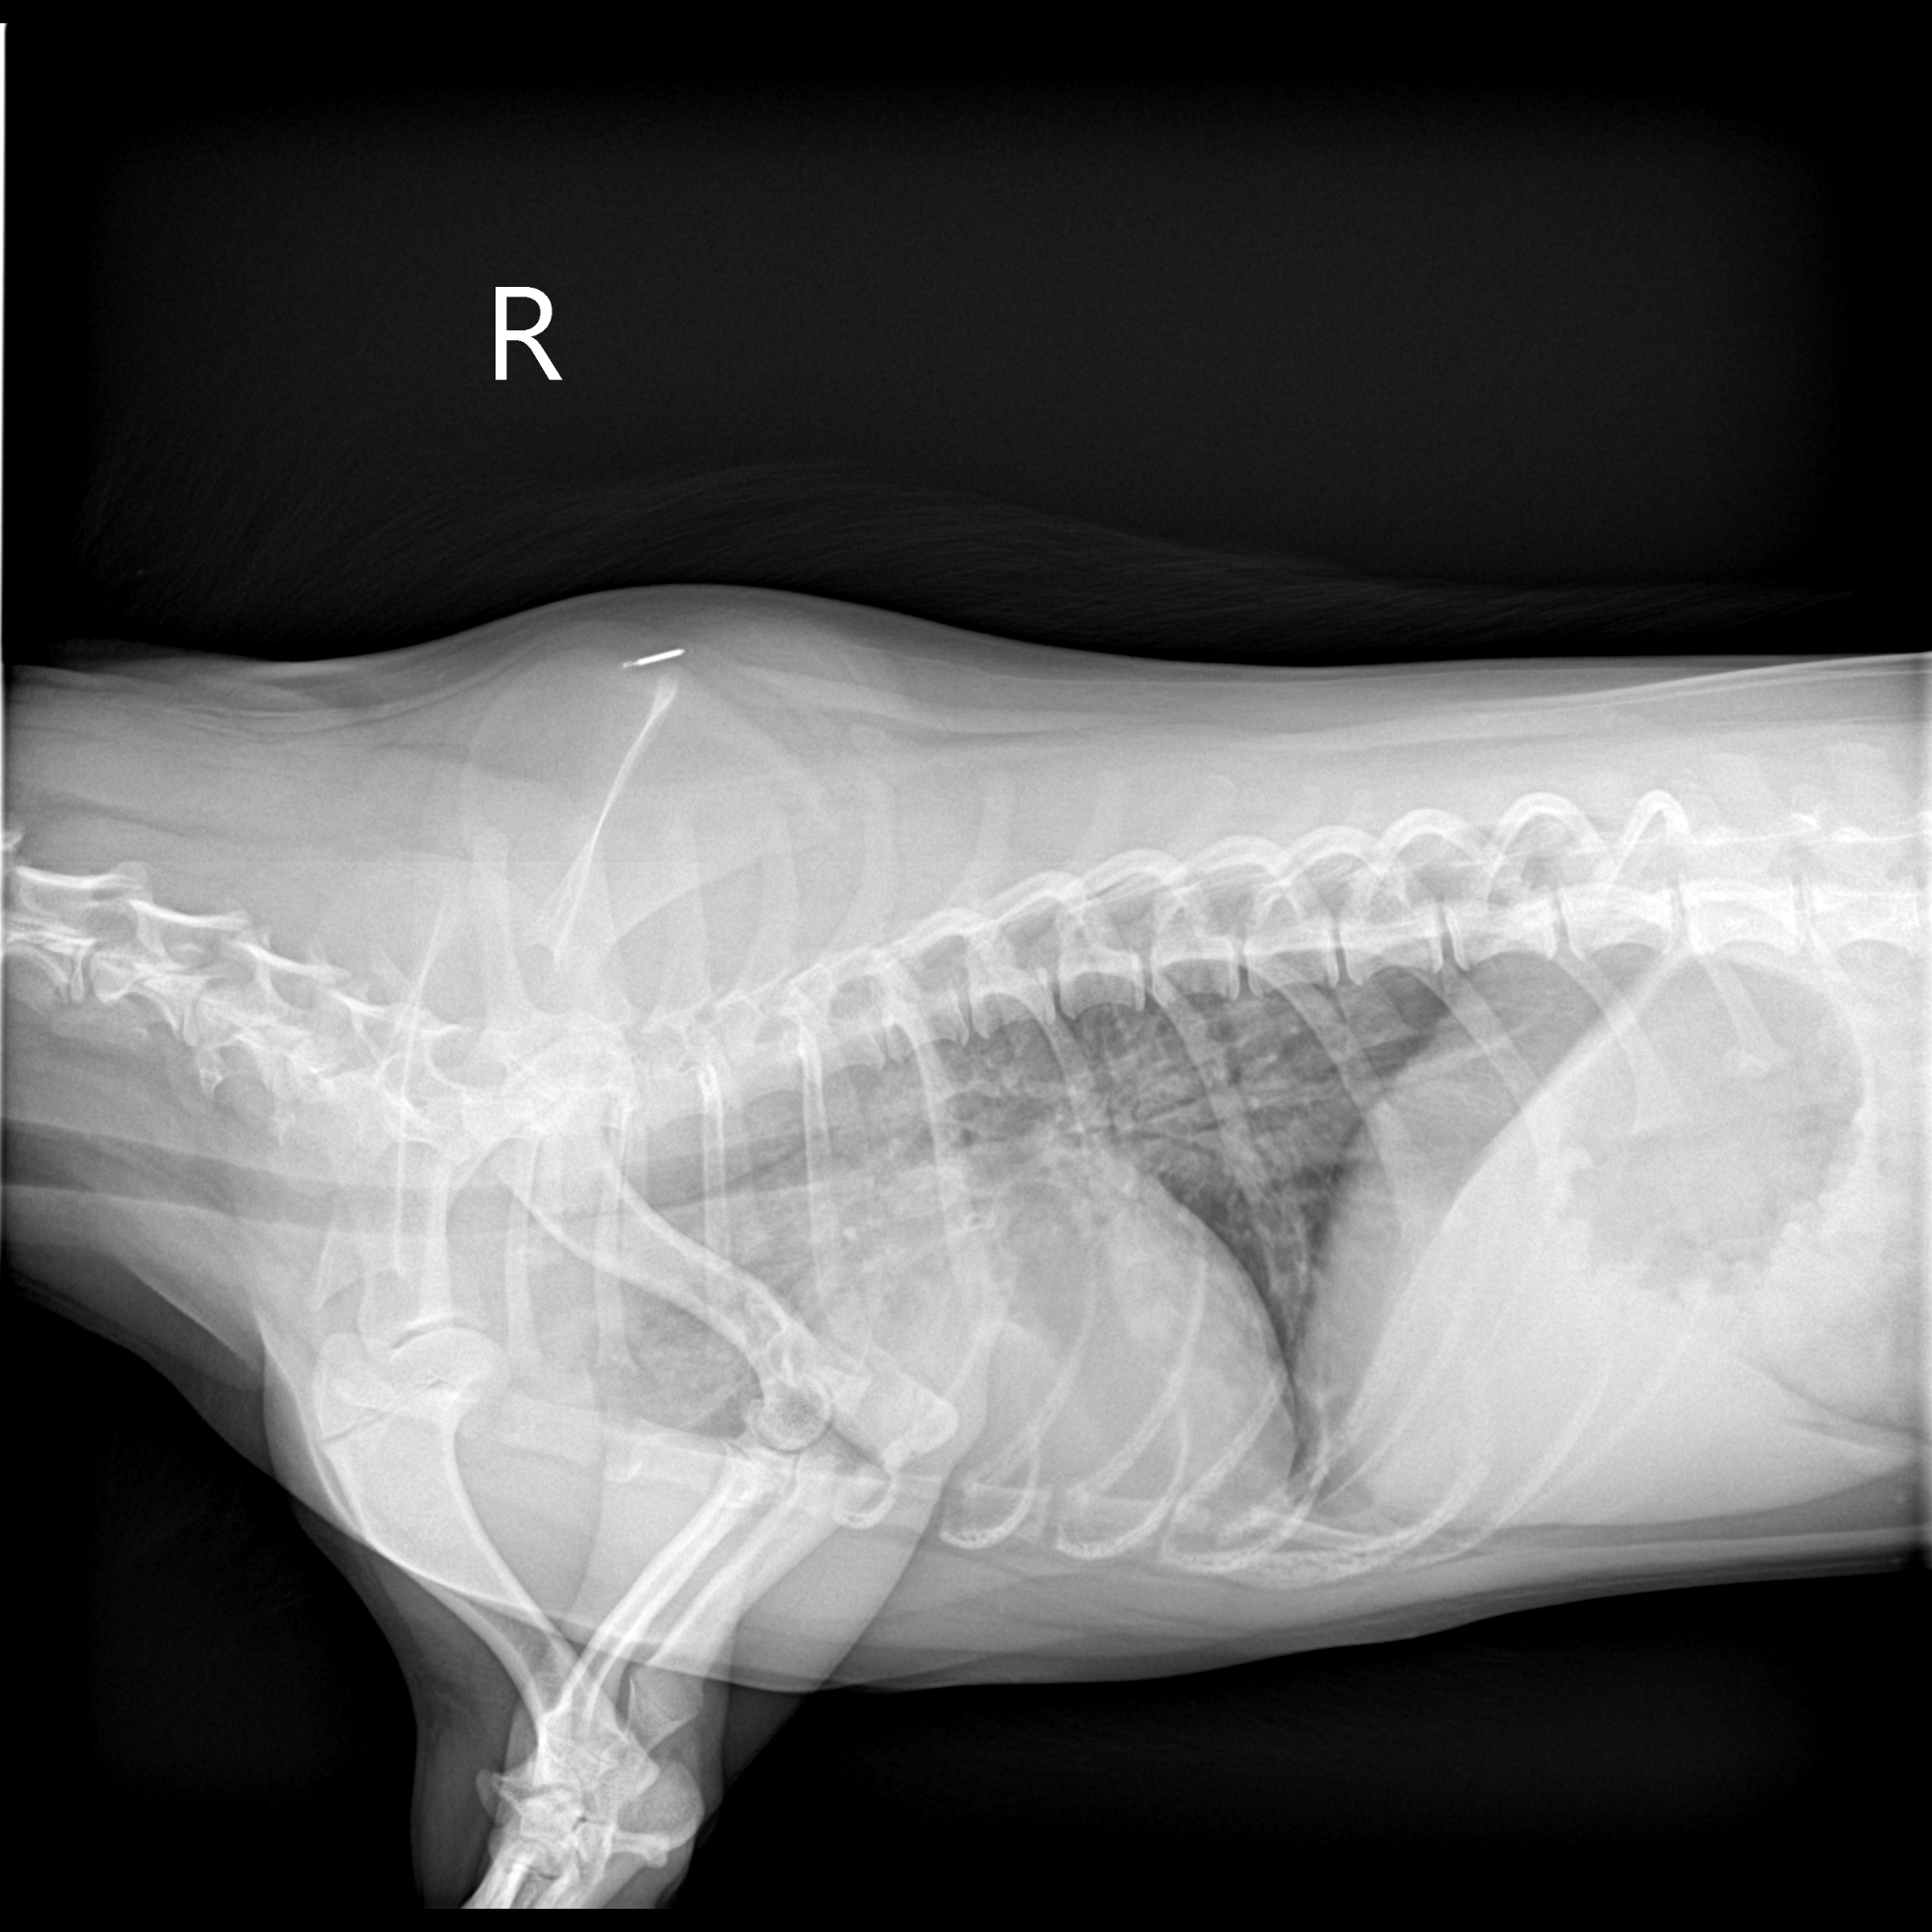

The emergency vet immediately took her into the back and put her into an oxygen cage because of how hard she was working to breathe. After reviewing her records and xrays, they revised her diagnosis to aspiration pneumonia, likely just from drinking water. Vega now had a temp of 103.9. Since she was quickly getting sicker, the doctor wanted to switch Vega to a more broad-spectrum antibiotic (amox/clav) via IV/IM.

The ICU team did more xrays and said her pneumonia has gotten worse, though that's typical for pneumonia. Her temperature was 103.9 again. They did labs and put her back on IV fluids. Her doctor added a fluoroquinolone antibiotic. This is 3rd line treatment for aspiration pneumonia as it's pretty harsh and can cause teeth and joint issues, but the xrays showed that the amox/clav needed extra help.

10/6 she had another follow-up at the dogtor where I was told her lung xrays looked "great" and we could stop her nebulizer treatments and aggressive antibiotics. At this appt, her PCP was on vacation and the practice owner was the one seeing her.

Yesterday (10/24) she went back to the dogtor, simply because her eyes looked a little glassy and she'd coughed twice. She saw her PCP this time, and after xrays etc I was told her aspiration pneumonia had likely NOT been fully cured, was back, and was worse. At this point we need to do a tracheal wash under sedation so cultures can be done of whatever is causing this infection, and the abx can be narrowed down. however she has to be off abx for 4-6 weeks. so we go back in 2 weeks to do that, along with bloodwork and more xrays. she'll be back on albuterol breathing treatments in the meantime.